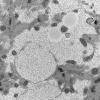

Pompe Disease (4)